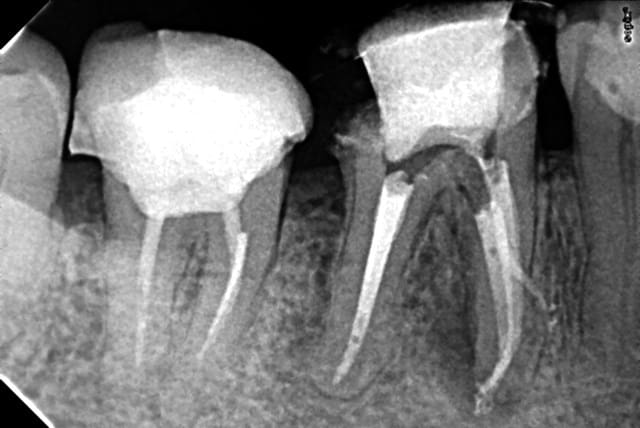

Je reviens sur ce cas à l'image curieuse. patient venu en urgence et je m'étais démerdé pour faire le TT en un RDV quitte à modifier quelque peu mon planning de la journée ( léger retard).

Ben le patient n'est pas venu pour la suitte ( consult pour faire le tour de la bouche)

Rendez vous dans un an en urgence pour l'extraction. Que j'adresserais au stomato. -)